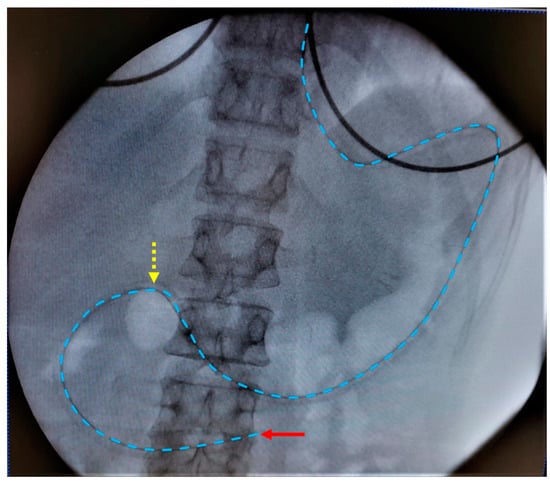

2.3. Study Protocol